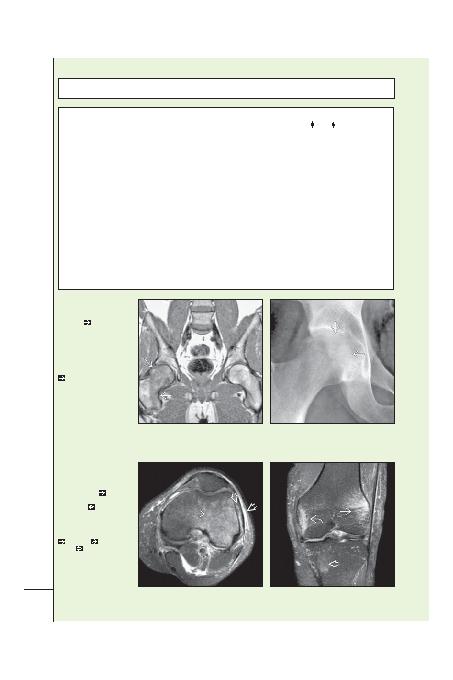

(Sol) Koronal T1A yb MR

kesitinde sa femur baindan

femur boynuna uzanan kemik

ilii ödemi

. Subkondral

düük sinyal ve eklem yüzeyde

düzensizlik yok. (Sa) Ayni

hastanin ÖA radyografisi

femur baindaki difüz

osteopeniyi gösteriyor. Eklem

yüzeyin kortikal kemiinin

görünürlüünde azalma

mevcut. Asetabulum

etkilenmemi ve eklem aralii

korunmu. GBO tanisi MR

ve radyografik bulgularin her

ikisini de gerektirir.

(Sol) Bölgesel gezici

osteoporozlu bir hastanin

Aksiyel T2A yb MR kesiti.

Lateral femoral kondilde

yaygin ilik ödemi

mevcut

ve hafif yumuak doku

deiiklikleri

izleniyor.

(Sa) Ayni hastanin birkaç ay

sonraki koronal T1A yb MR

kesiti. Ödem paterni deimi;

lateralde boyutu azalmi

, medyalde

ve proksimal

tibyada

yeni ödem mevcut.

Bölgesel gezici osteoporoz

1 eklemden dierine ya da

bu olguda olduu gibi ayni

eklemde bir lokalizasyondan

dierine göçebilir.